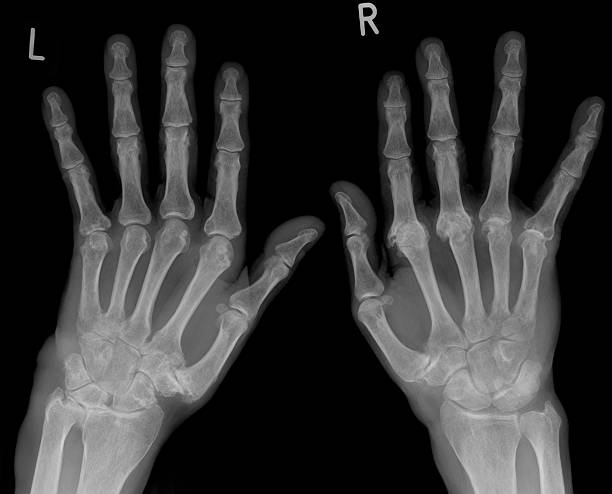

류마티스 관절염(Rheumatoid Arthritis, RA)은 자가면역 질환의 일종으로, 면역 체계가 자신의 관절을 공격하여 염증을 유발하는 만성 질환이에요. 시간이 지나면서 관절이 손상되고 변형될 수 있으며, 전신 피로와 통증을 동반하는 경우가 많아요.

| 대칭적인 관절염 | 양쪽 손, 발, 무릎 등 대칭적으로 관절염 발생 |

류마티스 관절염의 증상은 관절의 염증과 통증이 가장 대표적이지만, 전신적인 증상도 함께 나타날 수 있어요. 초기에는 미미한 불편함으로 시작되지만, 조기에 치료하지 않으면 관절 변형과 기능 저하로 이어질 수 있어요.

| 손가락 및 발가락 변형 | 심해지면 관절이 휘어지거나 변형될 수 있음 |

- 관절 변형 - 손가락과 발가락이 휘어지고 관절 기능 저하